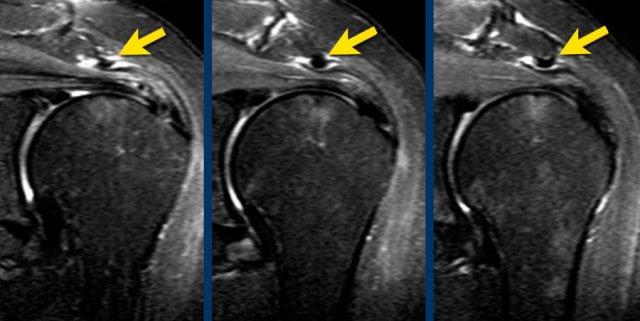

Hình ảnh là MRI khớp có thuốc tương phản từ chuỗi xung T1W xóa mỡ mặt phẳng coronal.

Hình ảnh cho thấy rách bán phần mặt khớp đoạn xa gân cơ trên gai hay còn gọi là rách bờ viền, cũng được gọi là tổn thương PASTA – bong gân bán phần mặt khớp gân cơ trên gai.

Đây là tổn thương PASTA ở một bệnh nhân khác.

Hình ảnh

Hình minh họa và MRI khớp có thuốc tương phản từ chuỗi xung T1 xóa mỡ mặt phẳng coronal.